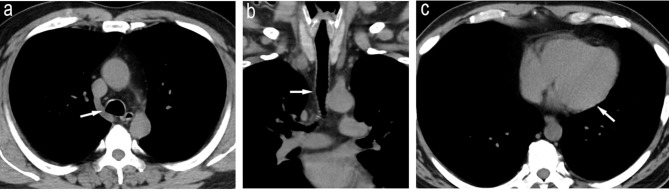

A 51-year-old Japanese man was diagnosed with left-sided ulcerative colitis (UC) at age 41. He was treated with mesalazine and azathioprine and maintained remission. At age 51, the patient developed bloody stools, abdominal pain, scleritis, arthritis, cough, bloody sputum, and pericardial effusion. Considering that pericardial effusion is an atypical extraintestinal complication of UC, and the patient met the diagnostic criteria for relapsing polychondritis (RP), a diagnosis of RP complicating a relapse of UC was made. Steroid therapy was administered, and both diseases improved. Golimumab, an anti-tumor necrosis factor-α inhibitor, was introduced as maintenance therapy for UC. All symptoms, including pericardial effusion, improved. Subsequently, no relapse of UC or RP was observed. As only a few cases of RP overlapping with UC have been reported and no treatment protocol has been established, we considered this case valuable and worthy of publication.